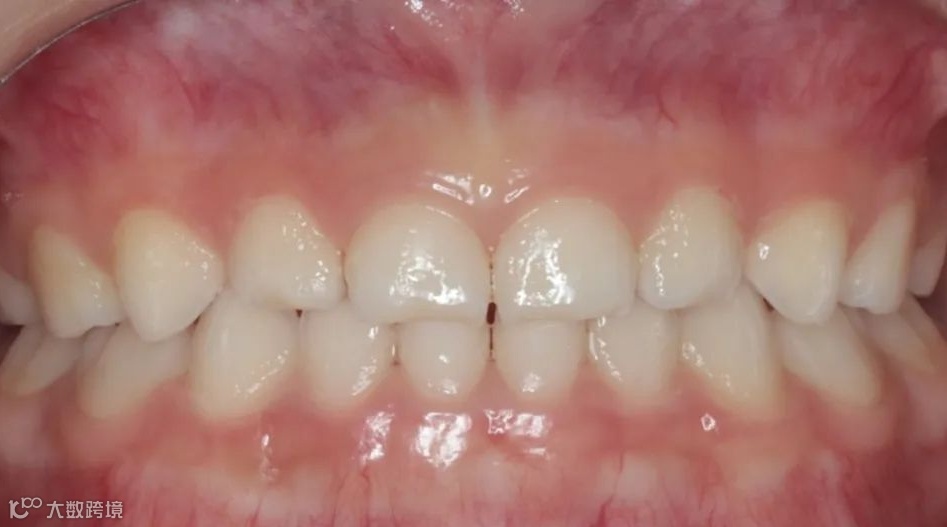

治疗后右侧咬𬌗相

治疗后正面咬𬌗相

治疗后左侧咬𬌗相